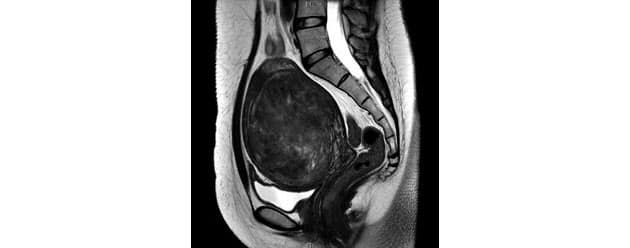

子宮筋腫 Mri画像 Before After 閲覧注意 いやすひと ヒカル 癒しと気づきが 必要なタイミングで届きます

子宮筋腫と卵巣腫瘍 その6 Mri 日々 楽天ブログ

Mri画像と病院探し 彡 子宮筋腫 激痛とのタタカイ 楽天ブログ

私の巨大子宮筋腫 Mri筋腫画像あり 妊娠6ヶ月で死産した天使ママ 第二子妊娠中